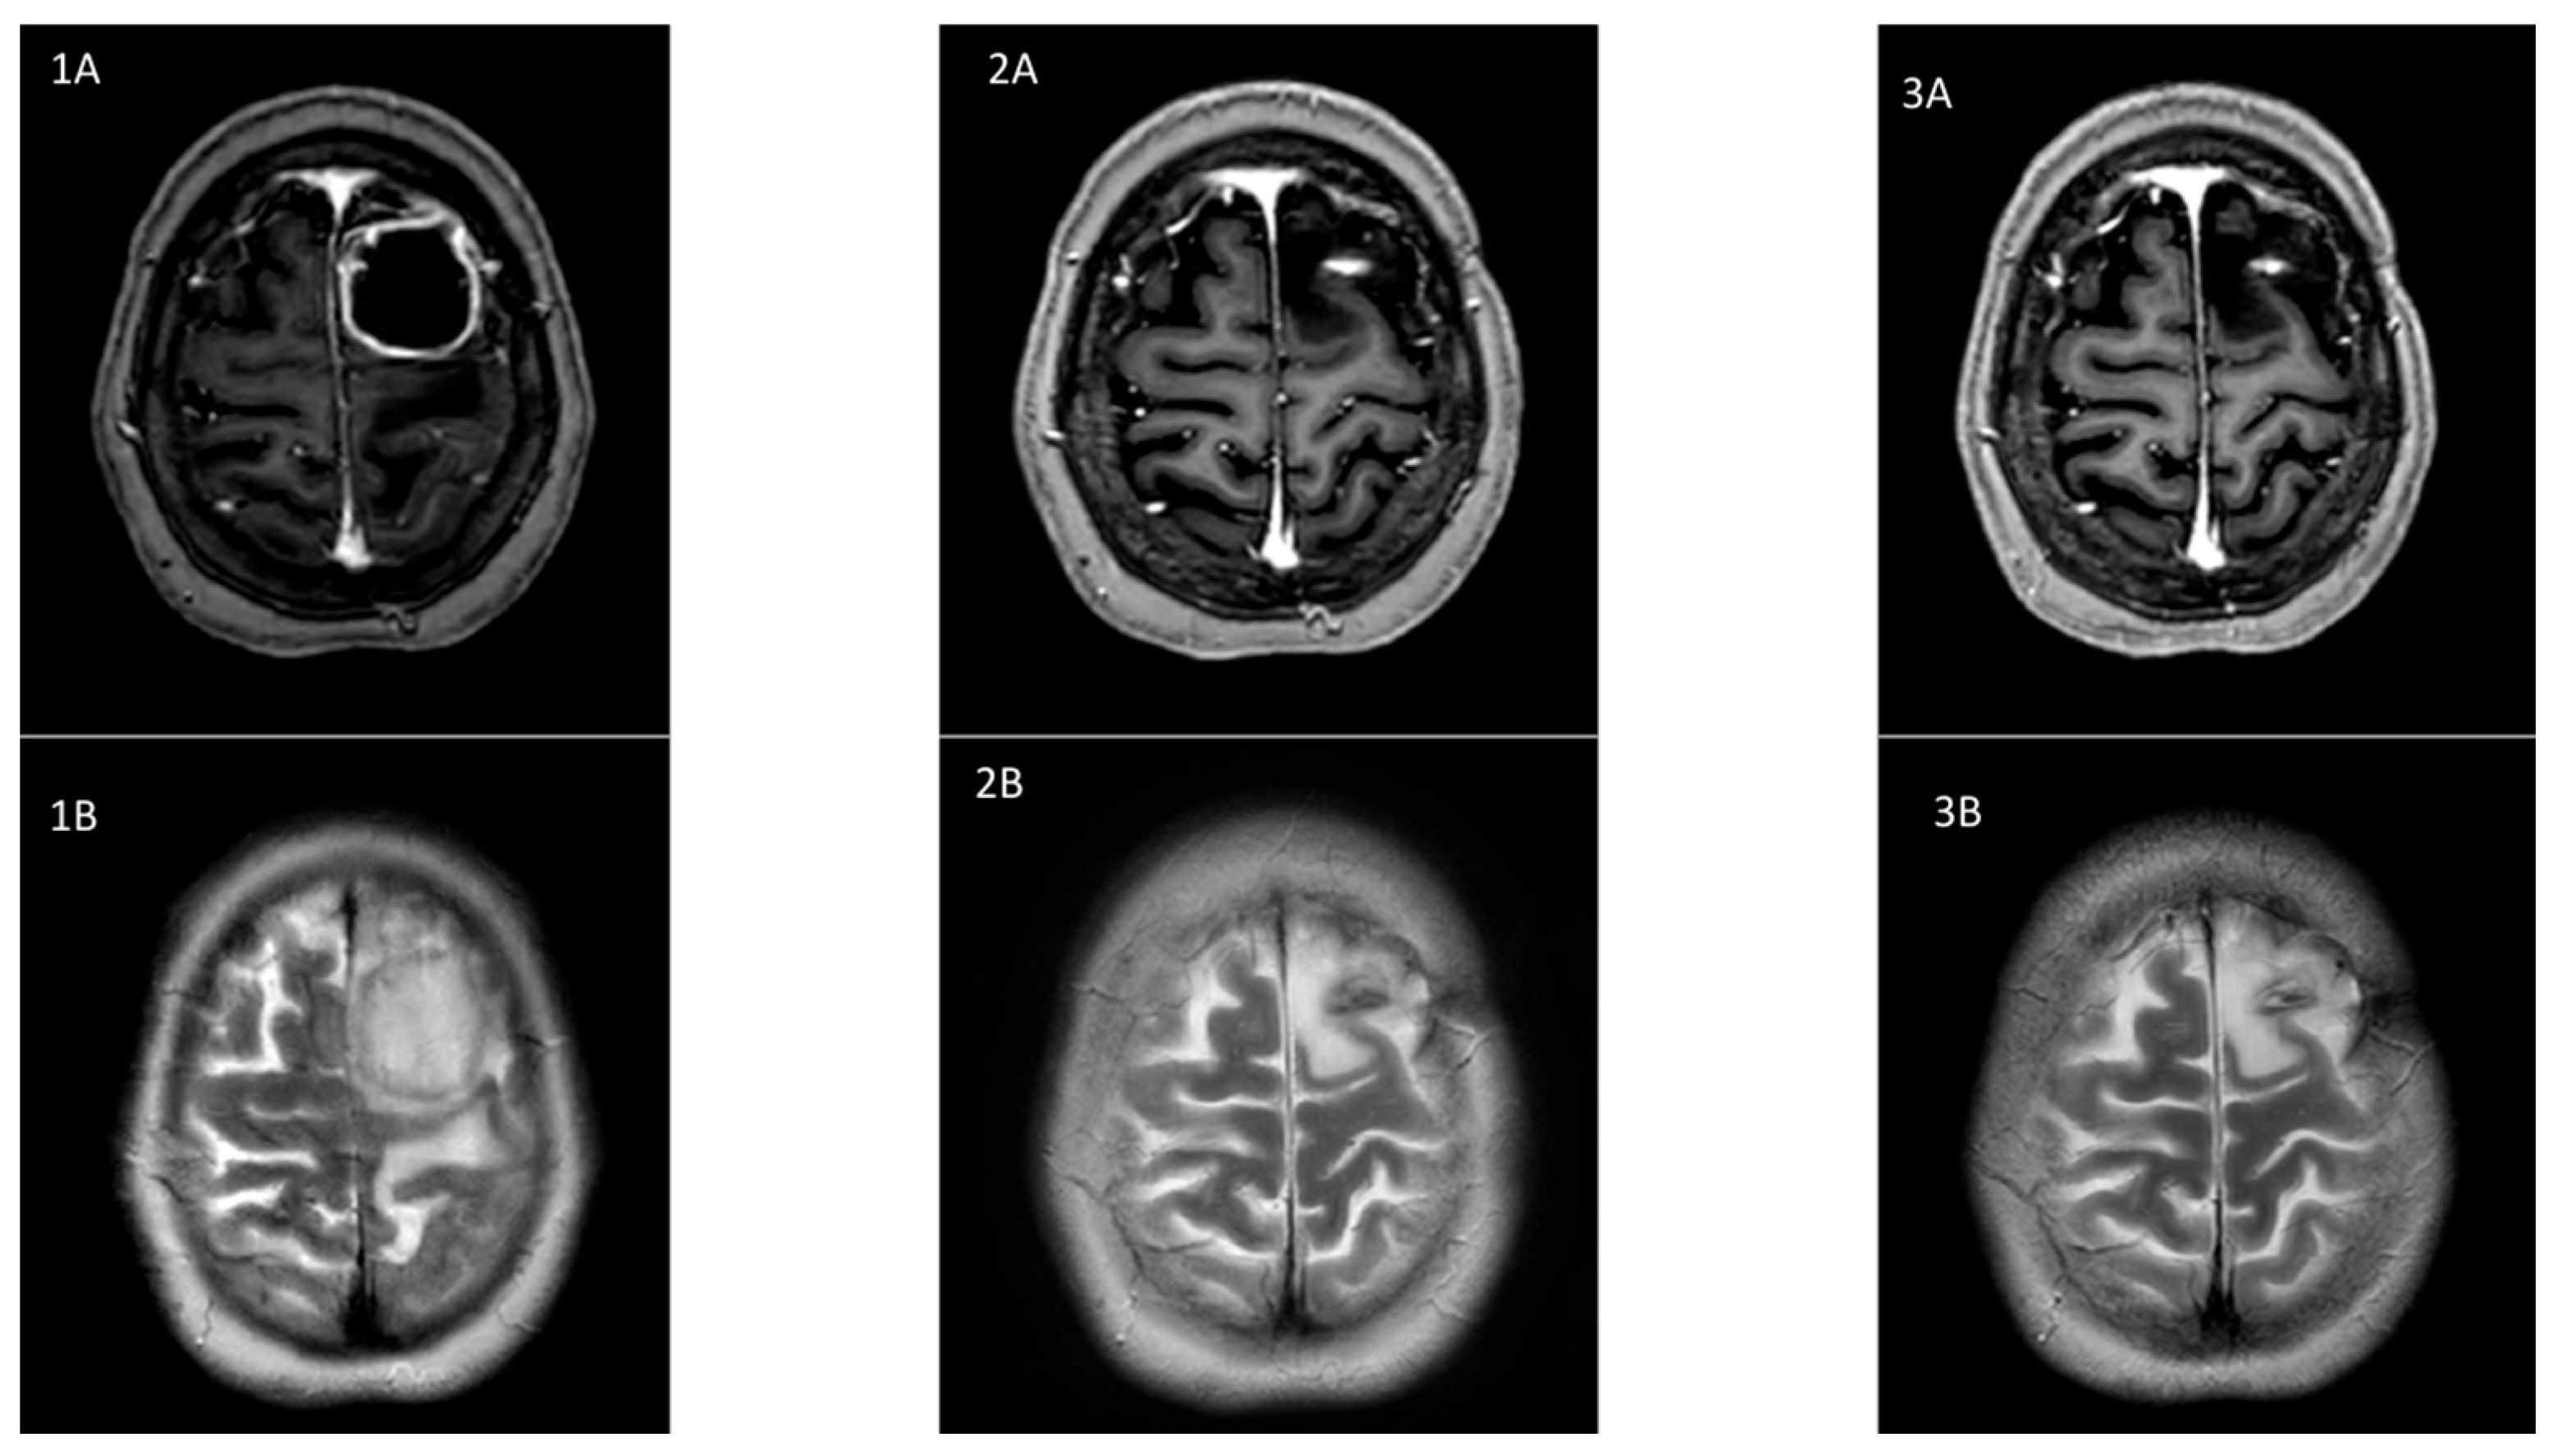

2. Case Report